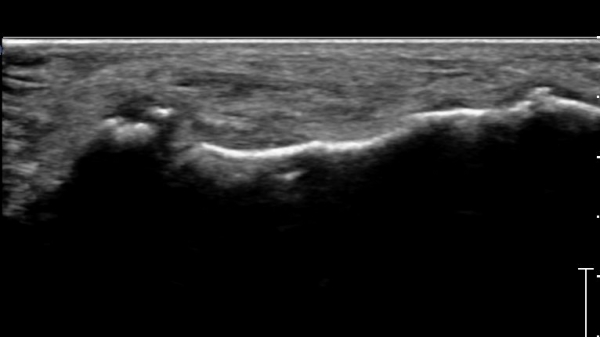

ÃÊÀ½ÆÄ°Ë»ç :  Àü°ÅºñÀδë Á¾´Ü¸é°Ë»ç¿¡¼­ Àü°ÅºñÀδëÀÇ Àú¿¡ÄÚ À§ÃàÀÌ °üÂûµÇ°í °Å°ñ °æºÎÀÇ °ß¿­°ñÀý ¹×

°Å°ñÁÖ»ó°ñ°üÀý ºÎÁ¾ÀÌ °üÂûµÈ´Ù(»çÁø 1).